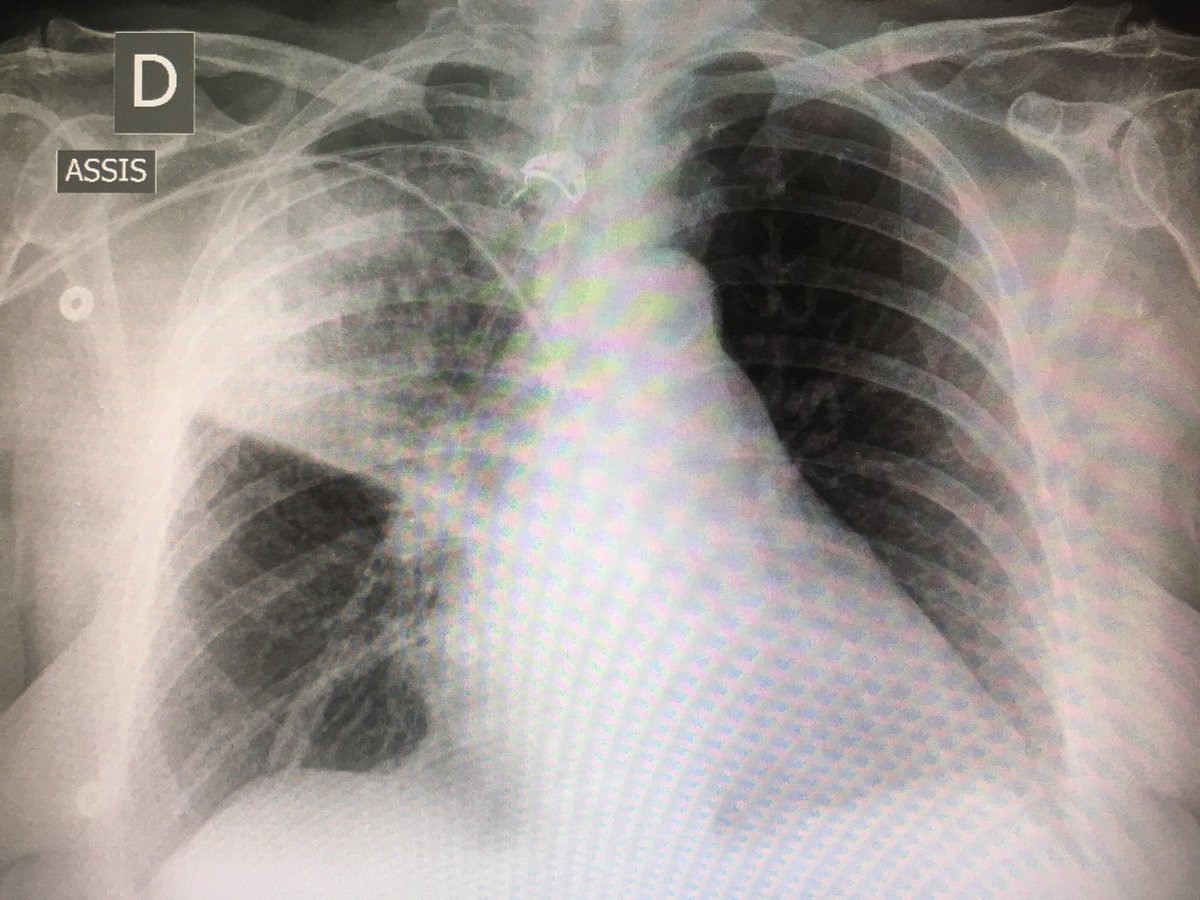

Légionellose Radiographie : Manifestations Pulmonaires Au Cours De L Infection Par Le Vih Demarche Diagnostique Sciencedirect : Radiographie du thorax de face et de profil;

Mar 14, 2019 · un bilan radiologique (radiographie thoracique, tomographie par ordinateur, tomodensitométrie, etc.), en cas d'hospitalisation, d'autres examens peuvent être réalisés, en particulier s'il existe des critères de gravité : Hémoculture, sérologie, etc.) fibroscopie pulmonaire avec prélèvements bactériologiques. Formes et présentations, composition, indications, posologie et Autres examens réalisables (consensus 2006) : Jun 25, 2021 · les informations sur le médicament humira 40 mg/0,4 ml sol inj en stylo prérempli sur vidal : Les infos, chiffres, immobilier, hotels & le mag. Radiographie du thorax de face et de profil; En difficulté diagnostique, le scanner thoracique sans injection peut être réalisé. Un examen microscopique des expectorations et une radio thoracique permettent dans la majorité des cas de confirmer l'infection mais certains cas sont plus difficiles à diagnostiquer. Antigène urinaire du streptoccocus pneumoniae. Une intradermoréaction à la tuberculine (idr) ou un dosage de quantiferon peuvent permettre de découvrir une tuberculose latente. Portail des communes de france : Jan 09, 2020 · la radiographie du poumon permet le diagnostic mais les images radiologiques sont parfois retardées de quelques jours par rapport aux signes cliniques.

Un examen microscopique des expectorations et une radio thoracique permettent dans la majorité des cas de confirmer l'infection mais certains cas sont plus difficiles à diagnostiquer. Les infos, chiffres, immobilier, hotels & le mag. Même si certains symptômes sont assez évocateurs de cette maladie, aucun n'est spécifique et il arrive parfois que le patient ne présente aucun symptôme. 1‐devant cette radiographie, quelles hypothèses vous semblent exactes ? Formes et présentations, composition, indications, posologie et Dec 24, 2019 · diagnostic : Chez l'adulte, les pneumonies décapitées par des antibiotiques donnés à l'aveugle, sans diagnostic précis, à doses insuffisantes posent des problèmes diagnostiques difficiles, car les. 1979) dont la plus connue est legionella pneumophila. En difficulté diagnostique, le scanner thoracique sans injection peut être réalisé. Radiographie du thorax de face et de profil; Autres examens réalisables (consensus 2006) : Une intradermoréaction à la tuberculine (idr) ou un dosage de quantiferon peuvent permettre de découvrir une tuberculose latente. Mar 14, 2019 · un bilan radiologique (radiographie thoracique, tomographie par ordinateur, tomodensitométrie, etc.), en cas d'hospitalisation, d'autres examens peuvent être réalisés, en particulier s'il existe des critères de gravité :

Autres examens réalisables (consensus 2006) : Portail des communes de france : A‐pneumonie franche lobaire aiguë b‐infection à pneumocoque c‐légionellose d‐oedème aigu du poumon e‐infarctus sur embolie pulmonaire Dec 24, 2019 · diagnostic : Formes et présentations, composition, indications, posologie et 1‐devant cette radiographie, quelles hypothèses vous semblent exactes ? Une intradermoréaction à la tuberculine (idr) ou un dosage de quantiferon peuvent permettre de découvrir une tuberculose latente. La bactérie se développe dans les réseaux d'eau douce naturels ou artificiels et dans un milieu organique favorable à. 46,363 likes · 113 talking about this. Antigène urinaire du streptoccocus pneumoniae. Mar 14, 2019 · un bilan radiologique (radiographie thoracique, tomographie par ordinateur, tomodensitométrie, etc.), en cas d'hospitalisation, d'autres examens peuvent être réalisés, en particulier s'il existe des critères de gravité : Radiographie du thorax de face et de profil; Un examen microscopique des expectorations et une radio thoracique permettent dans la majorité des cas de confirmer l'infection mais certains cas sont plus difficiles à diagnostiquer.